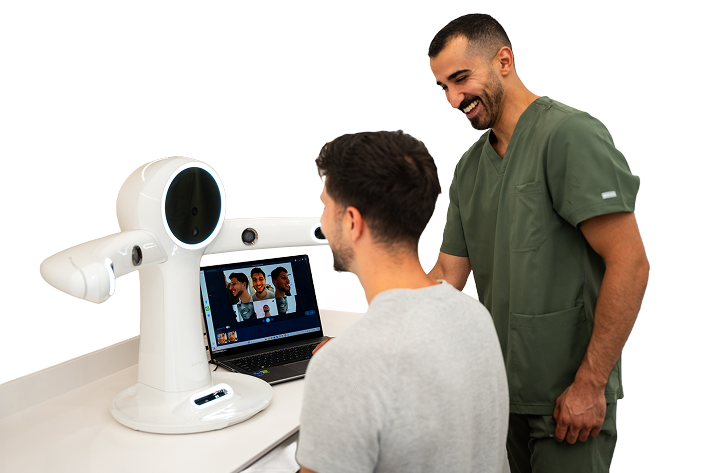

Utilizăm flux digital integrat – de la investigație până la realizarea lucrării finale. CBCT, scanare intraorală și analiză facială permit evaluare detaliată și plan adaptat fiecărui pacient.

Scanarea facială 3D captează proporțiile și conturul feței, integrând aceste date în planificarea dentară digitală. Astfel, forma și poziția lucrării sunt stabilite în raport cu structura dento-facială a fiecărui pacient.

Scanarea intraorală creează un model digital 3D al dinților și gingiilor, fără utilizarea amprentelor clasice. Imaginile sunt vizualizate în timp real, permițând evaluare precisă și ajustări imediate în planul de tratament.